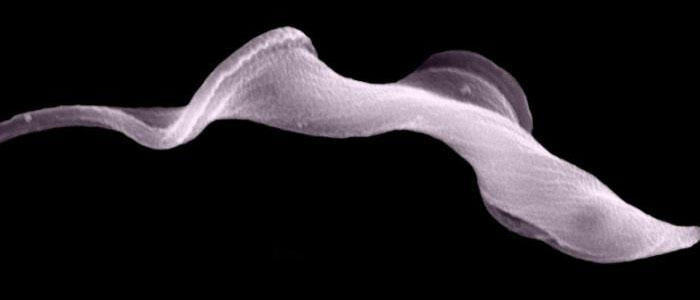

Scientific breakthrough could explain how superbugs rapidly evolve

Thu, 11 Oct 2018 19:01:00 BST